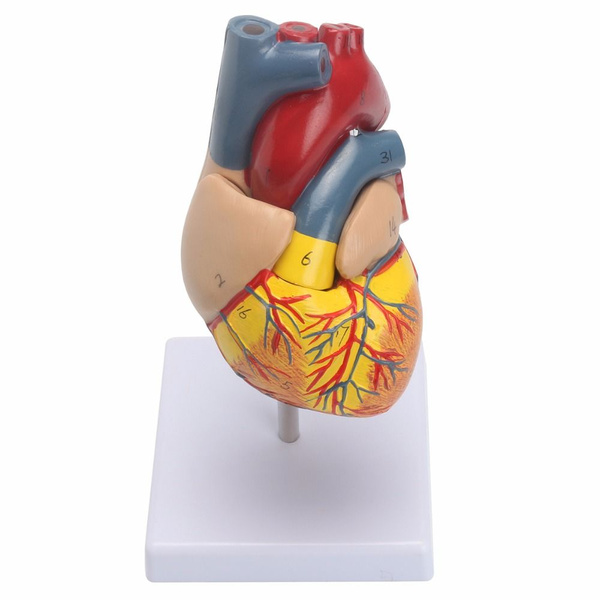

Фотографии и 3D-модели анатомии сердца человека